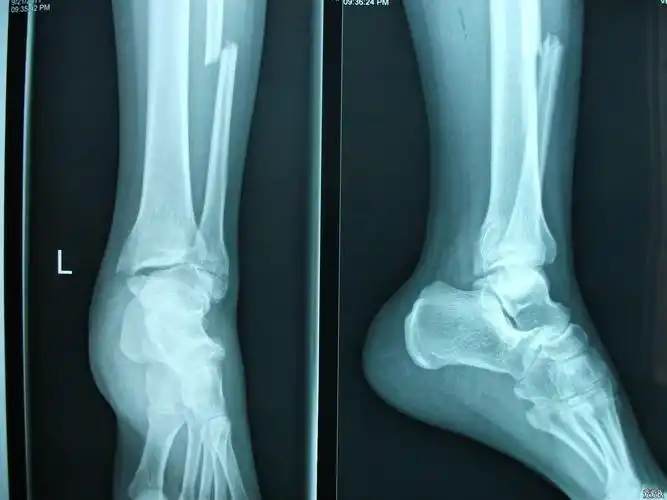

踝关节骨折一例

右脚踝扭伤,腓骨骨折,关节移位.请看x光片,谢谢.